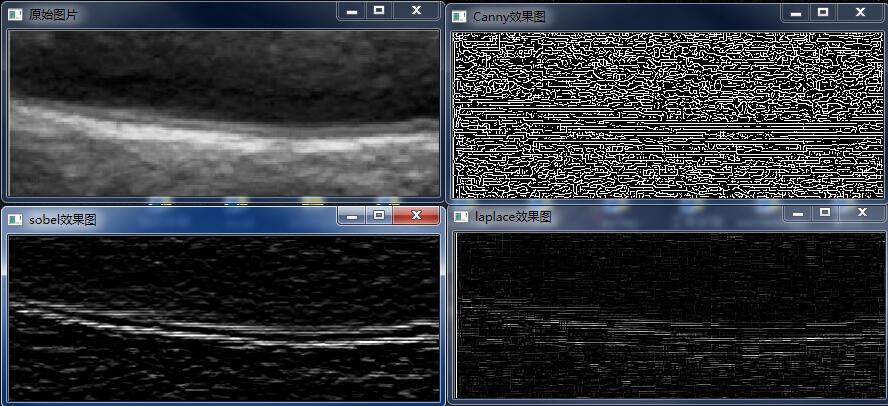

2、边缘检测

经典的边缘检测是以原始图像为基础,对图像的各个像素考察它的某个区域内灰度阶跃变化,利用边缘邻近的一阶或二阶方向导数变化规律做检测边缘。常用的边缘检测方法有:差分边缘检测、梯度边缘检测、Roberts 边缘检测算子、Prewitt 边缘检测算子、Sobel 边缘检测算子、Laplace 边缘检测算子等。在opencv中这些函数都是自带的:

Mat src = imread("C:/Users/Administrator/Desktop/4.jpg");imshow("原始图片",src);Mat dst0,dst1,dst11,dst2,dst22,dst3,dst33;//高斯滤波消除噪声// GaussianBlur(src, src, Size(3, 3), 0, 0, BORDER_DEFAULT);//转换为灰度图cvtColor(src, dst0, COLOR_RGB2GRAY);//HistD(dst0);//使用Laplace函数//第三个参数:目标图像深度;第四个参数:滤波器孔径尺寸;第五个参数:比例因子;第六个参数:表示结果存入目标图Laplacian(dst0, dst1, dst0.depth(), 3, 1, 0, BORDER_DEFAULT);//计算绝对值,并将结果转为8位convertScaleAbs(dst1, dst11);imshow("laplace效果图", dst11);Canny(dst0,dst2,3,9,3);convertScaleAbs(dst2, dst22);imshow("Canny效果图", dst22);Sobel(dst0,dst3,dst0.depth(),0, 1,3, 1, 1, BORDER_DEFAULT);convertScaleAbs(dst3, dst33);imshow("sobel效果图", dst33);

一般我们使用sobel算子进行滤波,很多算子存在在研究中 在实际应用中由于性能问题被淘汰。